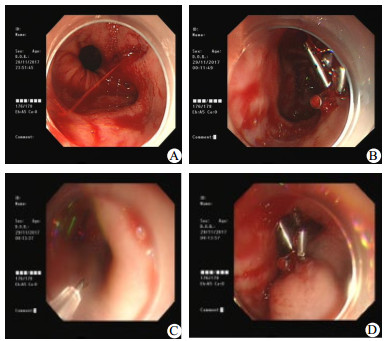

患者,男,67岁,因“乙状结肠癌术后造口状态9个月余,拟行造口回纳”于2017年11月23日收住入院。入院后完善各项检查,血压150/97 mmHg(1 mmHg=0.133 kPa),体温36.7 ℃,脉搏81次/min,肛门指检:距肛6 cm以下未及肿块,指套未染血。腹部增强CT报告:直肠癌术后改变,右侧中下腹造瘘,左肾及肝脏多发异常强化灶,转移考虑;肝脏多发囊肿;右肾囊肿,两肾结石;前列腺增生伴钙化。患者因拟于2017年11月29日行造口回纳术,11月28日19:00开始术前常规口服复方硫酸钠聚乙二醇散,共2盒,每盒药含有A/B包,将第1盒A/B包倒入量杯中,泡2 000 mL水,0.5 h内先喝1 000 mL复方硫酸钠聚乙二醇散溶液,自觉无腹痛腹胀后,剩下1 000 mL仍在0.5 h内喝完。喝完2 000 mL泻药后,进行腹部按摩,室内散步活动,待开始排便后,将第2盒A/B包倒入量杯中,泡2 000 mL水,缓慢喝泻药,2 h内喝完。该患者于家中19:00口服复方硫酸钠聚乙二醇散1 800 mL后,自觉胃部不适,约20:00左右,患者呕吐鲜红色胃内容物约1 000 mL,遂急送至病房,测血压86/53 mmHg,脉搏112次/min,立即心电监护、吸氧,输液港上港,开通两路静脉通路,医嘱予以林格液1 000 mL,万汶30 g静脉补液,潘妥洛克40 mg静脉滴注护胃治疗,酚磺乙胺750 mg静脉滴注止血治疗,急诊查血常规、凝血功能,备红细胞及血浆,请消化内科急会诊,予以插胃管进行胃肠减压,生理盐水500 mL+去甲肾上腺素40 mg,胃管内缓慢注入,患者呕血未缓解,持续呕血,量共计约3 000 mL,患者血红蛋白从入院时150 g/L下降至81 g/L,医嘱予行急诊胃镜下介入治疗,内镜下见贲门后壁撕裂,长约1.5 cm,予5枚钛夹夹闭裂口,黏膜下注射血管硬化剂聚桂醇5 mL后出血停止(图 1)。返回病房后,医嘱予输注红细胞2 U,血浆370 mL,禁食禁饮24 h后温凉流质饮食,72 h后进食半流质,未再出现呕吐和呕血,生命体征平稳,于12月3日出院。

| A:急诊胃镜发现贲门黏膜撕裂合并活动性出血点;B:钛夹夹闭出血点成功止血;C:出血点下方黏膜下注射硬化剂聚桂醇; D:黏膜下注射聚桂醇后巩固止血效果 图 1 患者急诊胃镜结果 |

胃镜检查为确诊本病的重要手段,胃镜检查最好在发病后48 h内进行[8]。按Forrest[9]分级为Ⅰ a级(动脉喷射样出血);Ⅰ b级(活动性渗血);Ⅱ a级(血管显露无出血);Ⅱ b(溃疡基底部附着血凝块);Ⅱ c(溃疡基底呈平坦的黑色状);Ⅲ(溃疡基底面洁净)。该患者镜下表现为Ⅰ a级,术中图片见图 1。而钛夹应用于上消化道内镜下止血治疗始于1975年,目前已得到广泛应用,技术亦日趋成熟[10]。